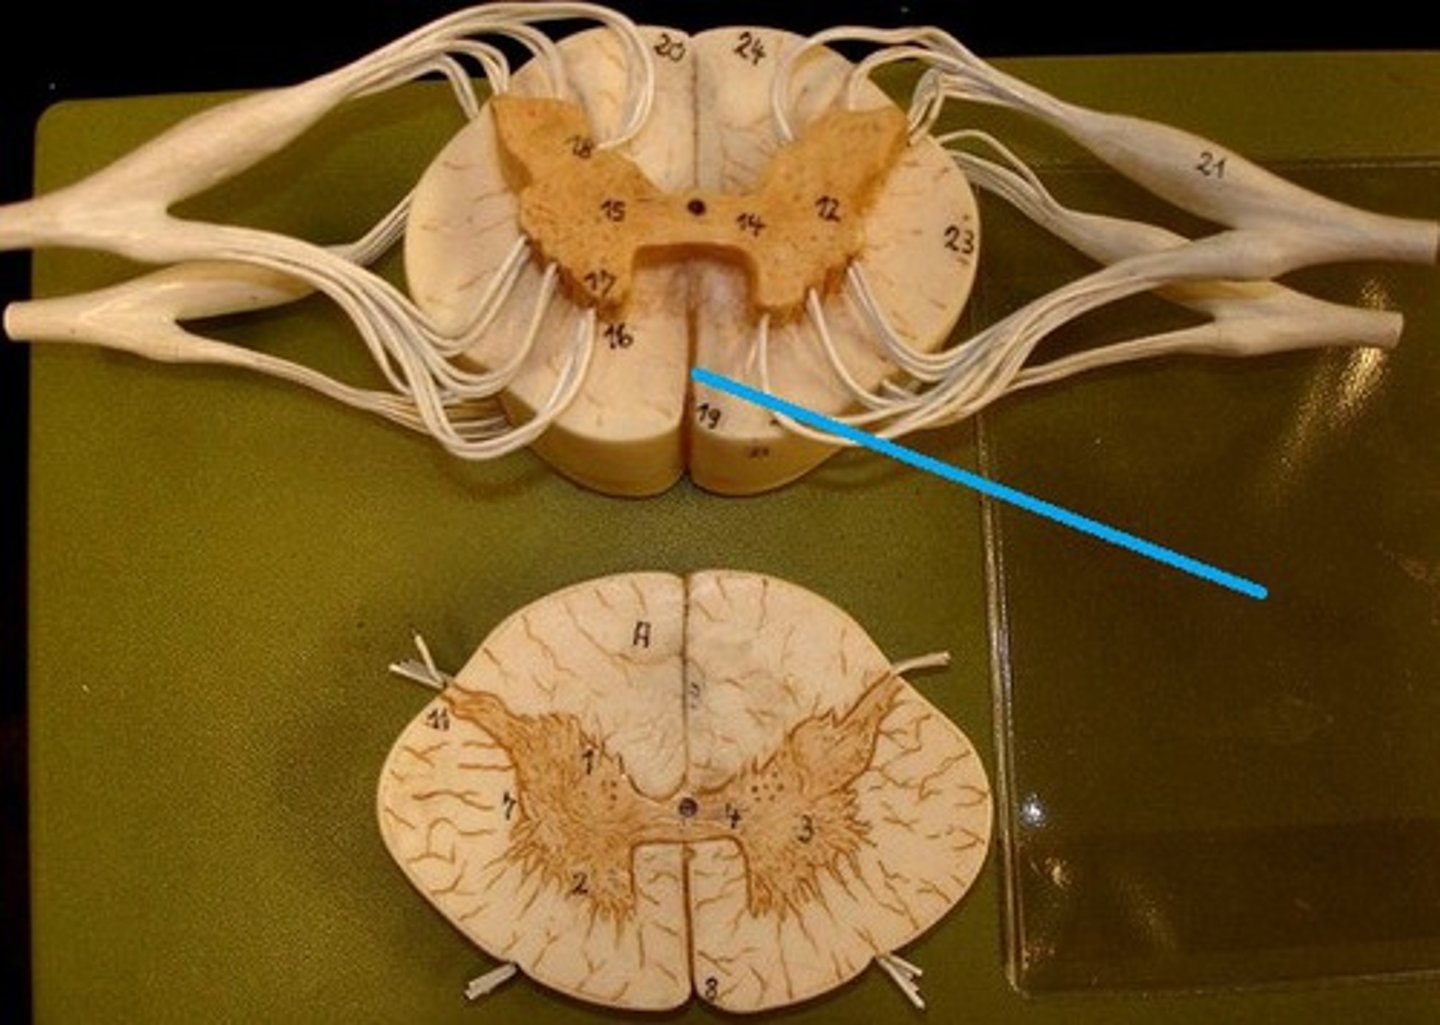

spinal cord

a major part of the central nervous system which conducts sensory and motor nerve impulses to and from the brain; housed within the vertebral canal

31 pairs of nerves arising from the spinal cord; letter abbreviation for region of spine they originate from; forms where the anterior and posterior roots join; mixed nerves (contain sensory and motor fibers)

posterior (dorsal) rootlets

merge to form a root

posterior (dorsal) root

contains sensory axons

posterior (dorsal) root ganglion

contains cell bodies of sensory neurons

true spinal nerve

anterior root

contains motor axons

conus medullaris

inferior tapered end of spinal cord

cauda equina

collection of spinal nerves below the end of the spinal cord; below L1 vertebrae

filum terminale

fibrous extension of the pia mater; anchors the spinal cord to the coccyx

spinal meninges

dura mater, arachnoid mater, pia mater (PAD to protect the spinal cord from deep to superficial)

dura mater (spinal cord)

thick, outermost layer of the meninges; 5 on image

arachnoid mater (spinal cord)

middle weblike layer of the meninges; 4 on image

pia mater (spinal cord)

thin, delicate inner membrane of the meninges; 3 on image

central canal of spinal cord

center of spinal cord which contains cerebrospinal fluid

posterior median sulcus

a shallow vertical groove dividing the spinal cord throughout its whole length in the midline posteriorly.

anterior median fissure

a groove along the anterior midline of the spinal cord that incompletely divides it into symmetrical halves

gray matter of the spinal cord

cell bodies, dendrites, and unmyelinated axons arranges in a butterfly shape with anterior and posterior "horns"

posterior (dorsal) horns

contain axons of sensory neurons and cell bodies (sensory nuclei) of interneurons